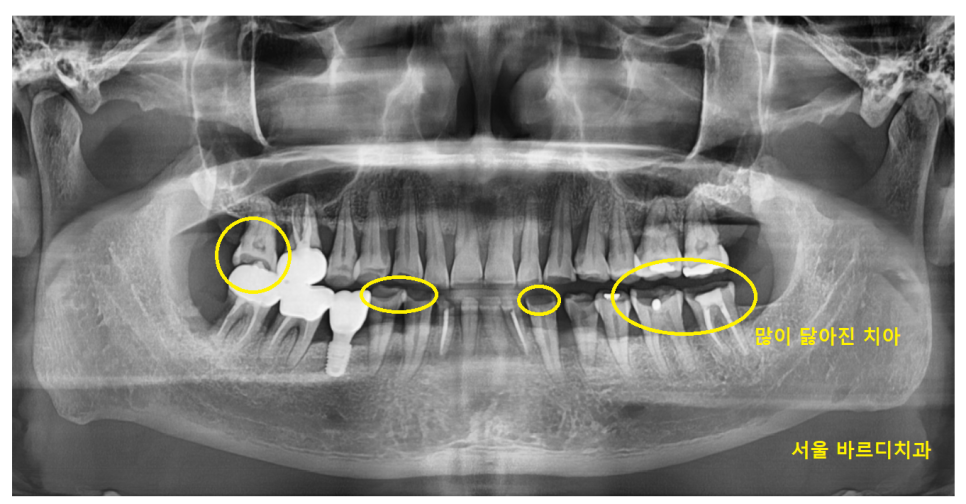

23.10.10

저희 병원을 처음 내원해주셨을 때

사진만 보고도 치아가 많이 닳으셨겠구나

보이더라고요.

▼실제 구강▼